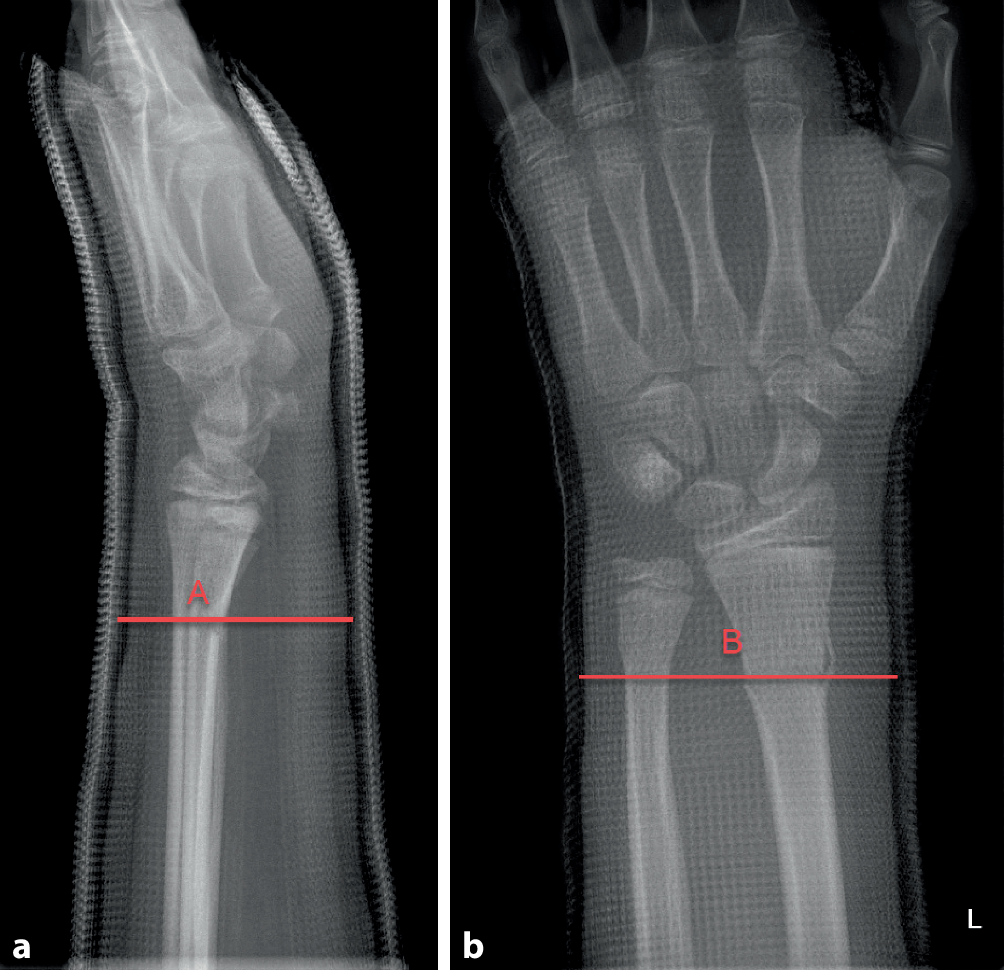

(Abb. 6 und 7)

Abb. 6

Damit ein Gips eine Fraktur zu halten vermag, muss er korrekt anmodelliert werden. Hierzu sollte das Wattepolster gleichmäßig verteilt sein und der Gips eng anliegen, ohne jedoch Druckstellen zu erzeugen. Das Anmodellieren des Gipses mit der flachen Hand, insbesondere im Frakturbereich, ist essenziell, erfordert jedoch etwas Übung und Erfahrung. Der Cast-Index ist ein Messwert, welcher zur Beurteilung des korrekten Anmodellierens herangezogen werden kann. Bestimmung des Cast-Indexes. Messung des Innendurchmessers (A) des Gipses auf Frakturhöhe im Seitenbild (a) geteilt durch den Innendurchmesser (B) des Gipses auf Frakturhöhe im a.-p. Bild (b). Optimal ist der Index bei 0,8 oder kleiner. Beachten Sie auch die durchgehende, gleichmäßige, aber nicht zu dick auftragende Polsterung

Durch Anmodellieren des Gipses mit flacher Hand wird der Gips in eine ovaläre Form gebracht. Hierdurch kommt es zum Aufspannen der Membrana interossea und somit zur zusätzlichen Stabilisierung der Fraktur. Es wird ein optimaler Cast-Index (s. Abb. 6a, b) erreicht. Des Weiteren liegt der Gips so dem Arm eng an und kann die Fraktur besser abstützen

Der Cast-Index ist definiert als der innere Durchmesser des Gipses auf Frakturhöhe im Seitenbild geteilt durch den inneren Durchmesser des Gipses auf Frakturhöhe im a.-p. Bild (s. Abb. 6 und 7). Er ist ein Messwert zur Kontrolle des korrekten Anmodellieren des Gipses [4] Ein Cast-Index unter 0,80 gilt als guter prognostischer Faktor mit geringerem Risiko der sekundären Dislokation bei Vorderarmfrakturen [3, 4]. Die Datenlage zum Cast-Index ist zwar bis heute sehr dünn und heterogen, mehrere Studien konnten jedoch den positiven Effekt für den Cast-Index nachweisen [2]. Damit kann dieser Parameter zur Beurteilung eines „guten Gipses“ im Alltag unserer Meinung nach durchaus hilfreich sein.